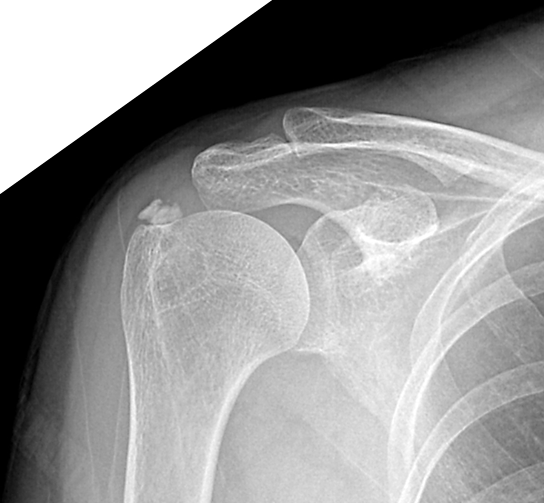

◈ 석회성건염의 진단은?

석회성건염은 X레이로 쉽게 찾을 수 있다. 이외에도 초음파, MRI로도 찾을 수 있다.